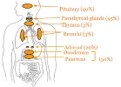

Endocrine neoplasia exemplified with MEN1 syndrome are distributed as parathyroid (90%), anterior pituitary (30% to 40%), pancreas or gastrointestinal tract (30% to 70%), adrenal cortex and thymus. Non endocrine tumours articulated with MEN1 syndrome are facial skin tumours such as angiofibromas or collagenomas, testicular epididymomas, lipomas, ependymomas, leiomyomas and meningiomas. Non syndromic neoplasm associated with MEN1 demonstrate somatic MEN1 mutations with frequencies such as glucagonoma (60%), vasoactive intestinal peptide adenoma (57%), non functioning pancreatic neuroendocrine tumours (44%), gastrinoma (38%), bronchial carcinoid (35%), parathyroid adenoma (35%), lipoma (28%), insulinoma (2% to 19%), angiofibroma(10%), anterior pituitary tumours (3.5%) and adrenocortical tumour (2%)1, 2. (Table 1, Table 2)

Figure 1, Figure 2, Figure 3, Figure 4, Figure 5, Figure 6, Figure 7, Figure 8

Figure 1.MEN1 syndrome demonstrating various components and neoplasm10.

Figure 3.MEN1 syndrome with proportionate distribution of classical neoplasm12.